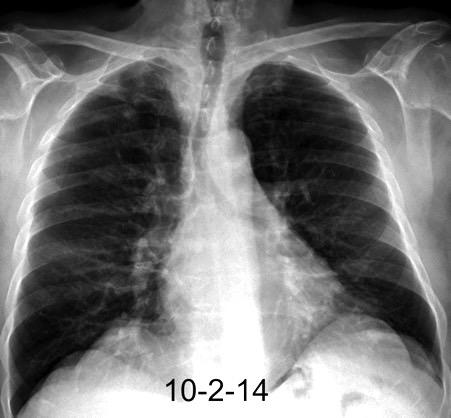

2. Hiperplasia de rebote.

Aumento de tamaño con tejido normal. Asociada a hipertiroidismo, sarcoidosis, aplasia de células rojas.

Más frecuente después de quimioterapia, quemaduras, stress

Masa intrabronquial de la pirámide del LII. Tumor carcinoide típico. Hiperplasia tímica

Nasseri F et al. Clinical and Radiologic Review of the Normal and Abnormal Thymus: Pearls and Pitfalls. Radiographics 2010